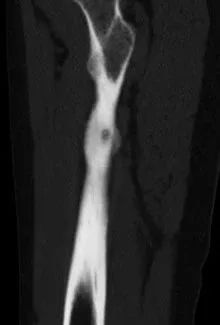

小陆病灶所在分布有重要的神经血管

经诊断,小陆同样患有骨样骨瘤。据其主治医生潘海文介绍,经影像学检查,病灶位于大腿中上段内后方,大腿内后方分布有重要的神经血管,加上瘤巢细小,直径仅约7毫米,术中探查犹如大海捞针。

小陆右腿检查片

此为横切面视角

术中,影像引导射频穿刺